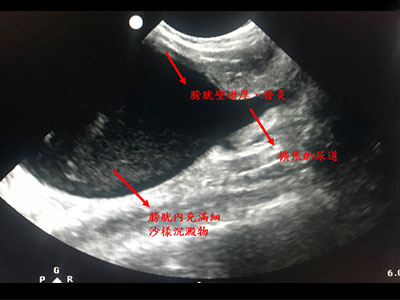

X光下動物泌尿道無明顯結石,超音波下發現膀胱壁增厚及發炎,腎盂、尿道擴張,膀胱內有大量結晶樣物質堆積。當下幫貓咪抽出70毫升之血尿,以緩解貓咪的疼痛不適、避免腎指數快速上升。